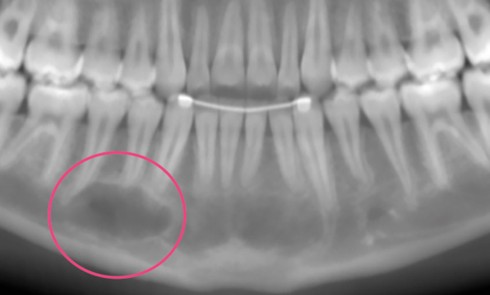

Focus sur le kyste osseux solitaire

Quelles manifestations cliniques doivent alerter le praticien ? Le plus souvent asymptomatique (fig. 2). Les dents en regard de la...Du plan axio-orbitaire (PAO) au plan Natural Head Posture (NHP)